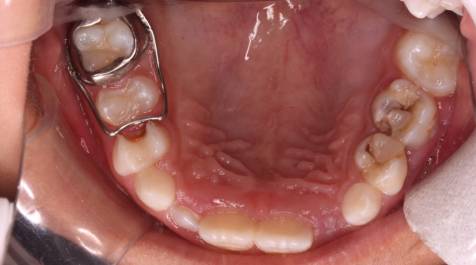

间隙保持器

间隙保持器就是指所有保持间隙的装置,有固定的和活动的。

常见的间隙保持器有:

丝圈式保持器、舌弓式保持器、腭弓式保持器、功能性保持器。

间隙保持器可防止邻牙向丧失部位倾斜和对领牙伸长,

保持早失牙齿的近远中和垂直的间隙,保证继承恒牙的正常萌出。

间隙保持器能保证恒牙正常生长